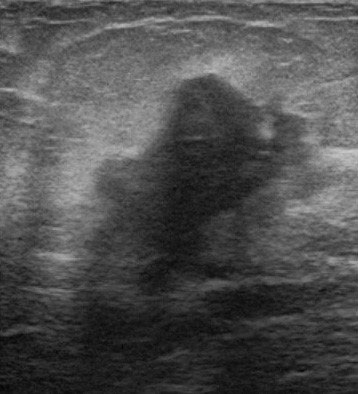

VAB超音波写真

乳腺診療には超音波検査が重要です。しこり、痛みなど乳腺の異常がある場合には診察と乳腺超音波検査を行い、実際にしこり(腫瘍など)があるかどうかを判断します。当クリニックでは富士フイルムヘルスケア社の超音波診断装置を使用しており、高周波プローブによって乳腺の繊細な画像検査が可能です。またリアルタイムエラストグラフィという機能でしこりの硬さを推定することができ、より正確な診断に役立ちます。

超音波検査で観察したしこりが乳がんを疑わず、良性疾患の可能性が高い場合には定期的な超音波検査による経過観察を行います。一方、しこりに悪性の可能性がある場合にはまず穿刺吸引細胞診(FNA:fine needle aspiration)を行います。これは注射に用いる針よりも細い針で乳腺のしこりなどから細胞を吸引し、顕微鏡で診断する検査です。この結果、悪性と判断されれば更なる精密検査を行い、乳がんに対する治療計画を立てていきます。FNAでも良悪性の判定が困難な場合や早期の乳がんが疑われ、ある一定量の組織採取が必要な場合には乳腺針生検を行います。当院ではより正確な診断をおこなうために、吸引をかけて組織を確保しながら針生検を行うVAB(vacuum-assisted breast biopsy)を行っています。FNAもVABも超音波検査で針の方向を確認しながら行います。